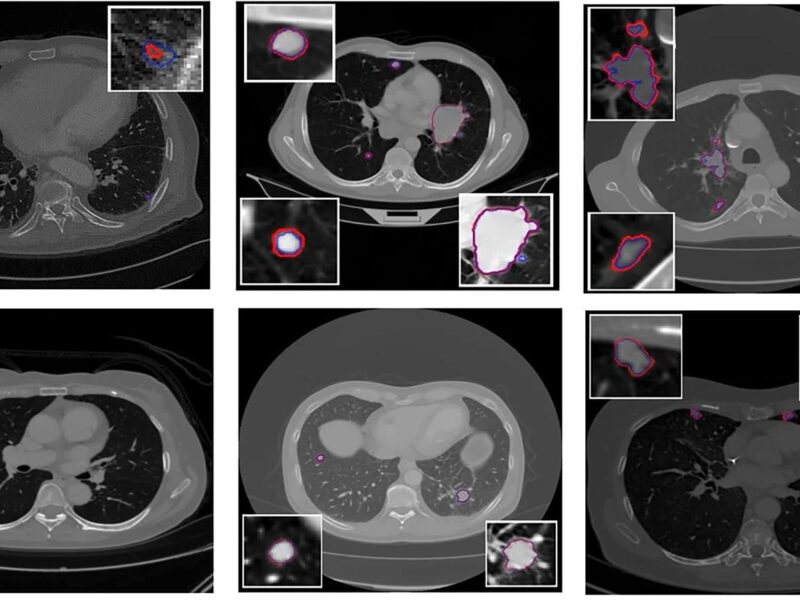

« Des radiologues spécialisés en imagerie thoracique ont confirmé que la qualité de l'imagerie et le contraste des tumeurs étaient comparables entre les images synthétiques et les images TEP réelles », déclarent les auteurs (photo d'illustration). D. R.

Grâce à l’apprentissage profond, des chercheurs du centre de cancérologie MD Anderson à Houston (États-Unis) ont généré des images TEP synthétiques à partir d’images de scanners thoraciques. Les résultats de leurs travaux ont été publiés en mars 2024 dans la revue Cell Reports Medicine [1].